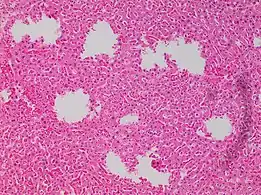

In microscopy, an artifact is an apparent structural detail that is caused by the processing of the specimen and is thus not a legitimate feature of the specimen. In light microscopy, artifacts may be produced by air bubbles trapped under the slide's cover slip.[1]

6. Image by Mikael Häggström, MD. Source for findings: Caroline I.M. Underwood, M.D., Carolyn Glass, M.D., Ph.D. "Lung - Small cell carcinoma". Pathology Outlines.{{cite web}}: CS1 maint: multiple names: authors list (link) Last author update: 20 September 2022